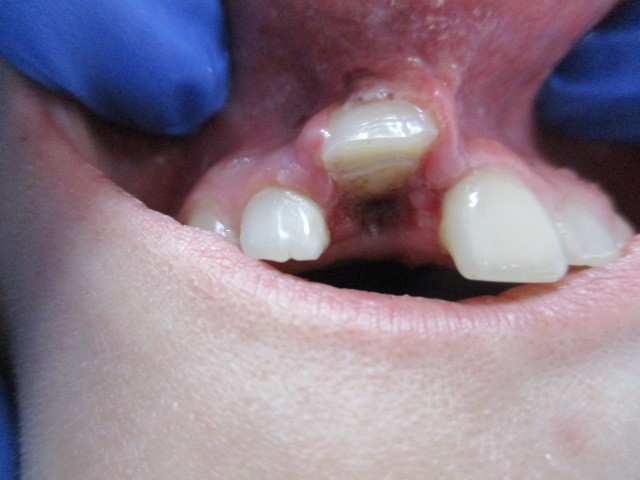

- W pracy przedstawiono przypadek złożonego urazu zęba stałego oraz postępowania bezpośrednio po urazie, który nastąpił na skutek przebytego napadu padaczki.

Streszczenie: W etiologii urazów zębów najczęstszymi przyczynami bywają upadek i uderzenie zębami o twardy przedmiot. Urazom zębów mogą towarzyszyć uszkodzenia: wyrostków zębodołowych, kości szczęki czy żuchwy, jak również tkanek miękkich powłok twarzy, warg, błony śluzowej jamy ustnej lub języka. U osób chorych na padaczkę stwierdza się urazowe uszkodzenie zębów, przy czym 1/3 takich przypadków wiąże się etiologicznie z napadami padaczki (1). W pracy przedstawiono przypadek złożonego urazu zęba stałego oraz postępowania bezpośrednio po urazie, który nastąpił na skutek przebytego napadu padaczki.

Summary: In the etiology of dental trauma the most frequent cause is hitting a hard object. Alveolar bone, maxillary or mandibular fractures, as well as facial soft tissue, lip, oral mucosa and tongue injuries may be co-incidental to dental trauma. Post-traumatic tooth injuries often occur in persons suffering from epilepsy. [...]